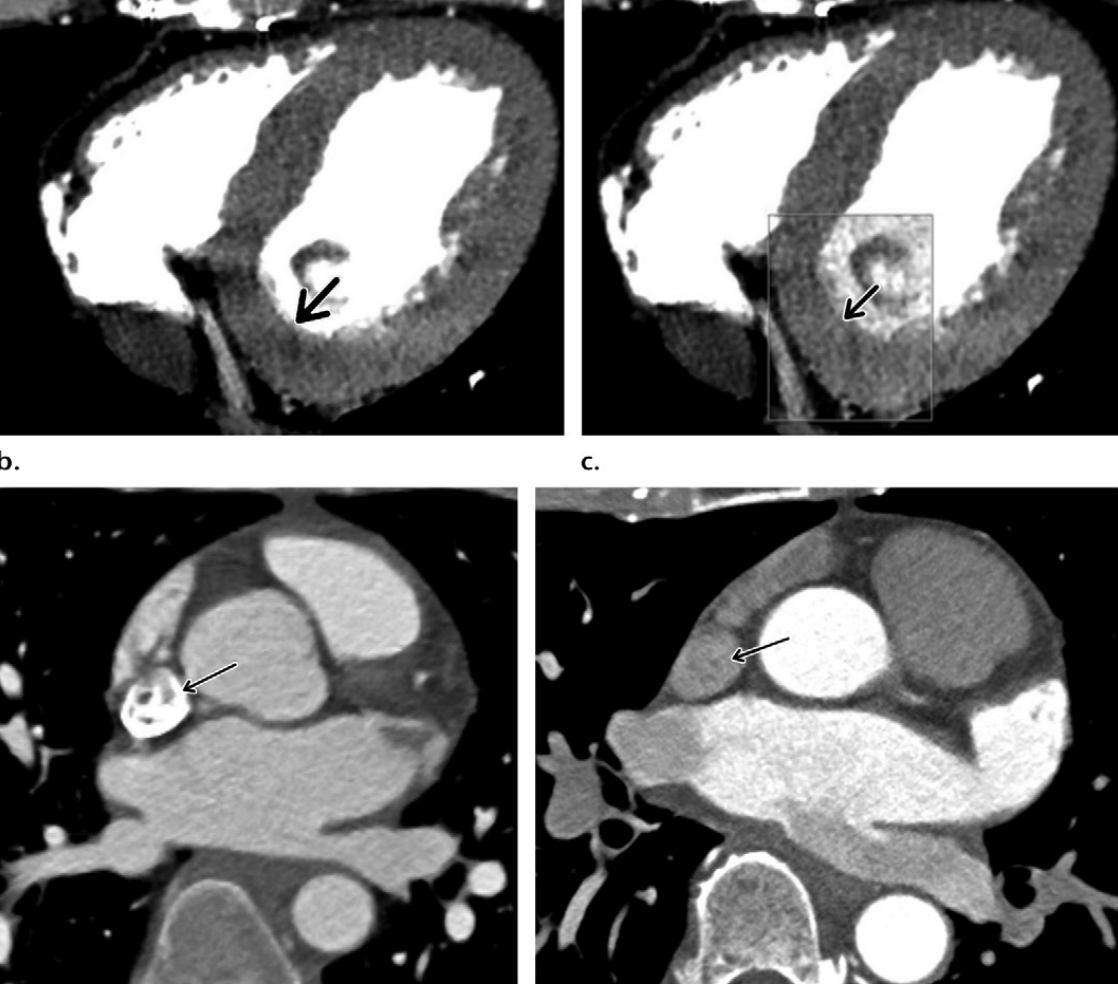

Based on the comparative appearance of these two images, what element of the reconstruction was modified during the second reconstruction?

Slice Thickness

Describe why slice thickness is so important in regards to coronary imaging